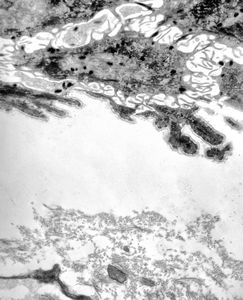

M, 1y. | epidermolysis bullosa … junctional type